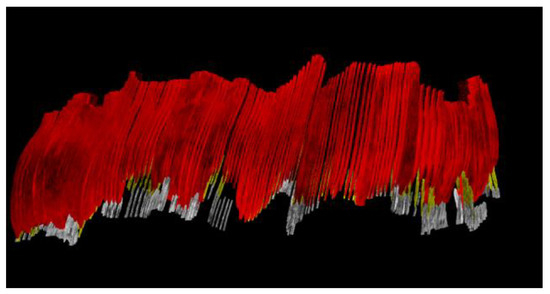

- Chifor, R.; Marita, T.; Arsenescu, T.; Santoma, A.; Badea, A.F.; Colosi, H.A.; Badea, M.-E.; Chifor, I. Accuracy Report on a Handheld 3D Ultrasound Scanner Prototype Based on a Standard Ultrasound Machine and a Spatial Pose Reading Sensor. Sensors 2022, 22, 3358. [Google Scholar] [CrossRef]

- Chifor, R.; Li, M.; Nguyen, K.-C.T.; Arsenescu, T.; Chifor, I.; Badea, A.F.; Badea, M.E.; Hotoleanu, M.; Major, P.W.; Le, L.H. Three-dimensional periodontal investigations using a prototype handheld ultrasound scanner with spatial positioning reading sensor. Med. Ultrason. 2021. [Google Scholar] [CrossRef] [PubMed]